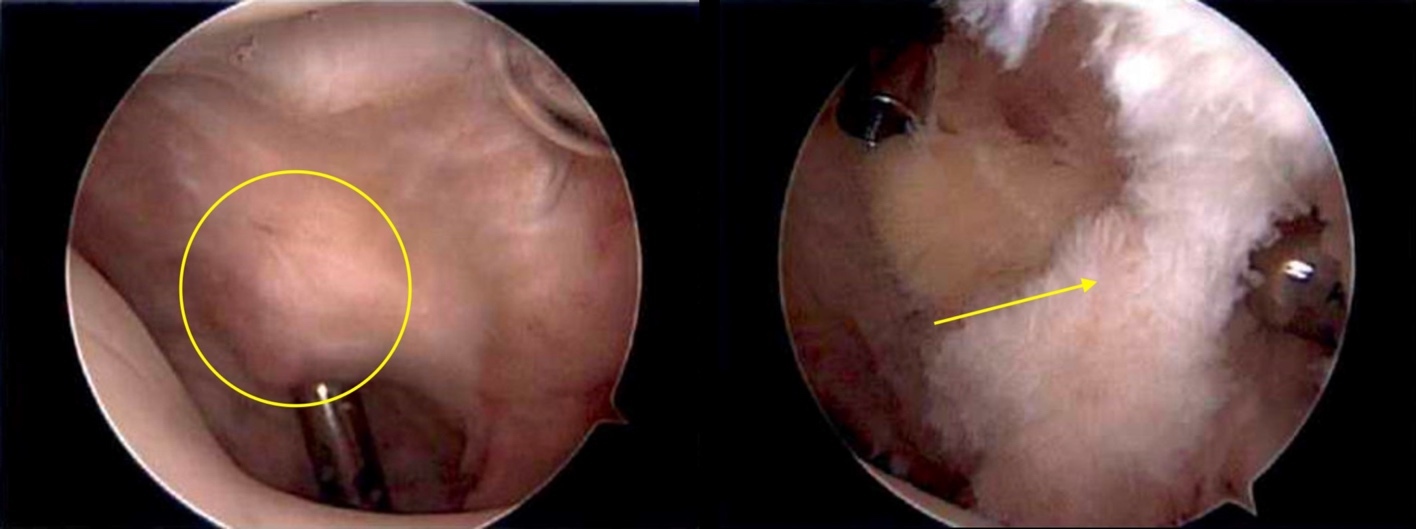

On exam she had pain to palpation of the anterolateral fat pat, with mild patellofemoral crepitus. Her range of motion was 0-130 degrees. Ligamentous exam was stable with full strength in quadriceps and hamstrings on manual muscle testing. Magnetic Resonance Imaging (MRI) demonstrated subtle thinning of the lateral patellar articular cartilage, fibrosis of the infrapatellar fat pad, and distension of the infrapatellar bursa (Figure 1). Otherwise, her MRI was unremarkable.

Arthroscopy was initiated with a superolateral viewing portal, established based on previously described technique,16 to better visualize the extent of infrapatellar fat pad fibrosis. With the use of Metzenbaum scissors through standard anterolateral and anteromedial portals, the interval between the fat pad and patellar tendon was developed. This freed any adhesions between the patellar tendon and the underlying fat pad tissues to reduce the risk of patellar tendon injury during debridement.

Through the superolateral portal view, a dense band of fibrotic scar tissue was identified on the posterior surface of the fat pad (Figure 2). With combination of basket punch and shaver, working through the anteroinferior portals, this scar tissue was resected in addition to approximately 70% of the remaining infrapatellar fat pad. A thin margin of fat pad was left in situ for protection of the overlying patellar tendon. The arthroscope was then placed in the anterolateral portal and a standard diagnostic arthroscopy was completed. The patient was noted to have some softening of the patellar cartilage in addition to a prominent lateral trochlear facet with relative medial trochlear facet hypoplasia. The remainder of her diagnostic exam was normal. Prior to exiting of the knee, tourniquet was released, and meticulous hemostasis of the remnant fat pad was established.